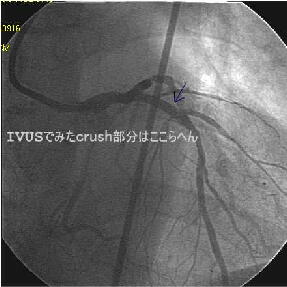

Crush�̎�Z�B

|

|

|

|